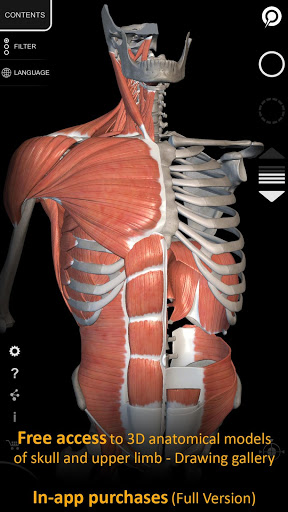

"Anatomy 3D Atlas" memungkinkan Anda mempelajari anatomi manusia dengan cara yang mudah dan interaktif.

Melalui antarmuka yang sederhana dan intuitif, Anda dapat mengamati setiap struktur anatomi dari sudut mana pun.

Model 3D anatomi sangat terperinci dan memiliki tekstur hingga resolusi 4k.

MODEL ANATOMI 3D

• Sistem muskuloskeletal